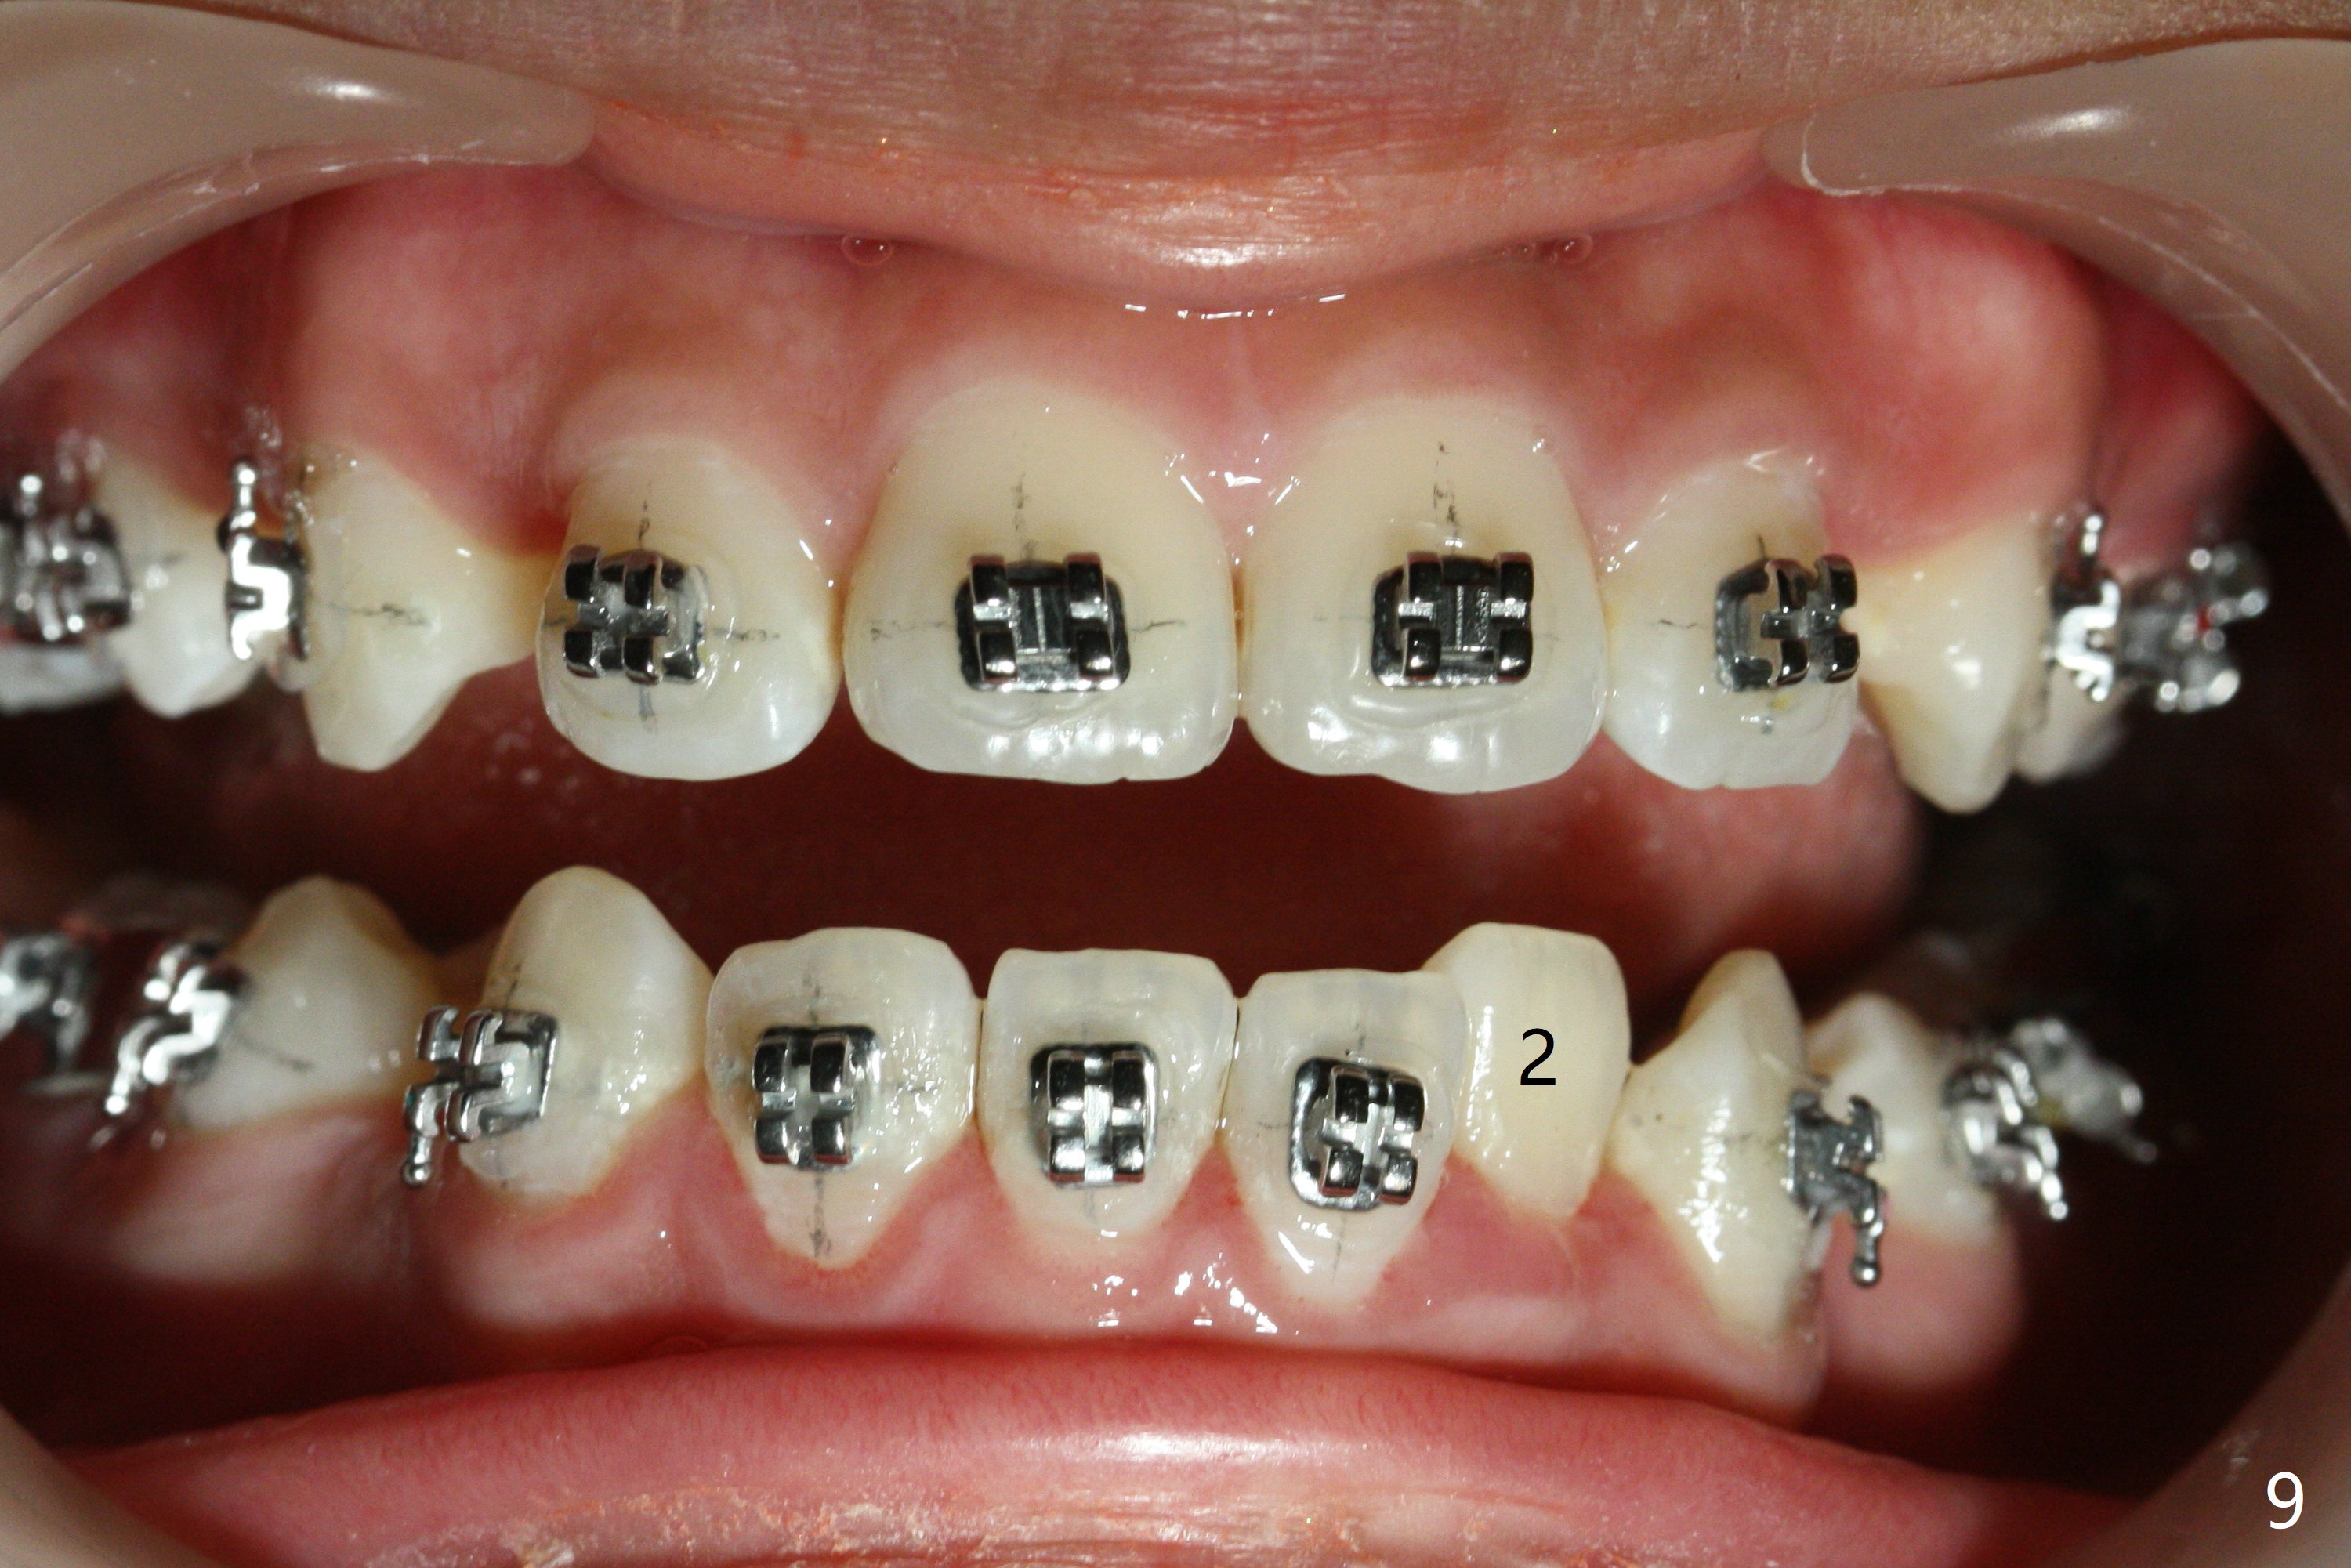

Due to moving out of state, the patient returns 2.5 months post last visit (5 months post banding). No sufficient space has been created for LL2 (Fig.9), while U3s have been distalized (quicker than the lower counterparts (because of soft bone)). The upper wire is changed to 18 niti without power chains, while the lower one remains 16 niti. Ligature wire is applied to LL5 and 6 as an anchor, while power chains of two are placed between LL3 and 5. Next visit add open coil spring between LL 1 and 3 for the lower midline correction as described above.